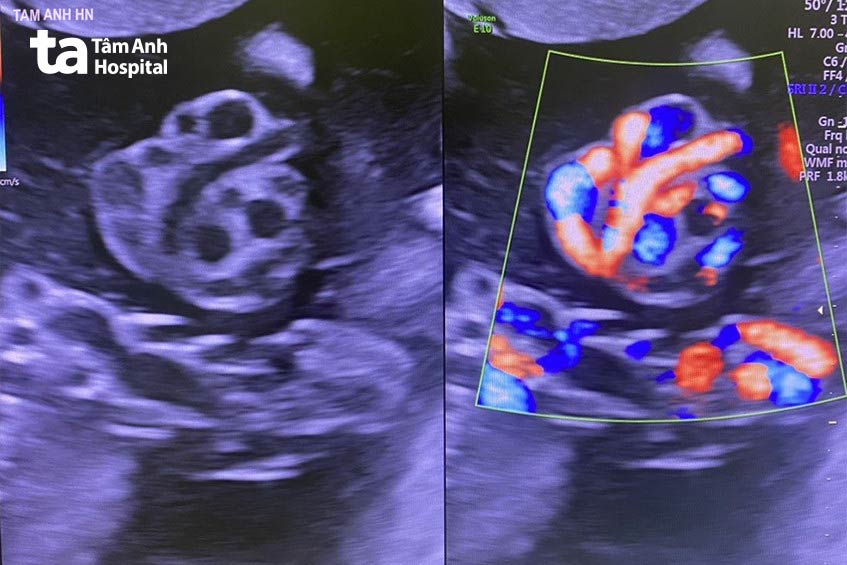

Ngày 24/5, ThS.BSNT Nguyễn Thành Vinh, Trung tâm Sản Phụ khoa, Bệnh viện Đa khoa Tâm Anh Hà Nội, cho biết, chị Trương Hải Ninh, 38 tuổi, ngụ tại Quảng Ninh phát hiện có nút thắt dây rốn ở tuần thai 31. Người bệnh được theo dõi thai kỳ chặt chẽ suốt 7 tuần; chỉ định mổ lấy thai kịp thời ở tuần 38 giúp thai nhi sinh đủ tháng khỏe mạnh.

Chị Ninh phát hiện dây rốn thắt nút qua siêu âm trong lần khám thai định kỳ, tình trạng không chặt, máu và oxy vẫn lưu thông tới thai. Bác sĩ chỉ định theo dõi chặt chẽ, khám thai mỗi tuần một lần, khám ngay khi bất thường.